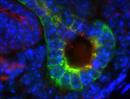

| Immunofluorescence of mutant 012-033-2 (E15.5) ureteric bud with very short cilia | Cplane1b2b012Clo/Cplane1b2b012Clo | C57BL/6J-Cplane1b2b012Clo |